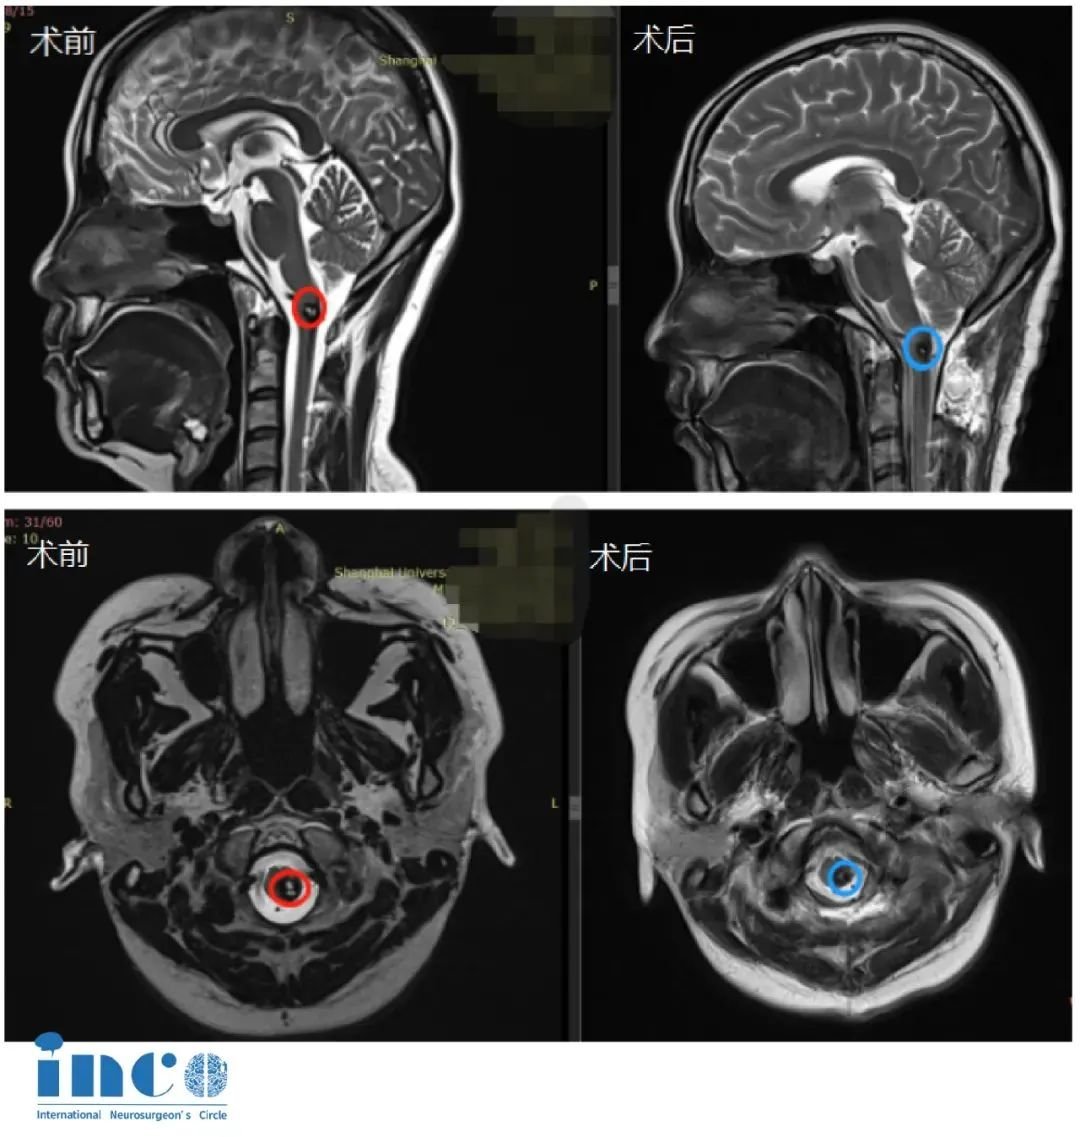

手术圆满成功,王女士在术后次日即拔管下地,两周后顺利出院——曾经被"手术瘫痪"阴影笼罩的王女士,竟以如此惊人的速度回归正常生活。术后MRI明确显示:延颈髓交界处的海绵状血管瘤已完全切除,十余年的致命威胁彻底解除。

术后两年后巴教授复查看片时评价:"结合既往出血史,当前病灶无复发迹象,稳定性良好。"

更令人振奋的是,2025年7月的最新MRI复查(见图)进一步验证了这一结果:海绵状血管瘤已经被完全切除,术区仅存手术相关的良性瘢痕及含铁血黄素沉积(均为此类术后正常表现),无任何神经功能缺损。而视频中的王女士行动自如、状态饱满。